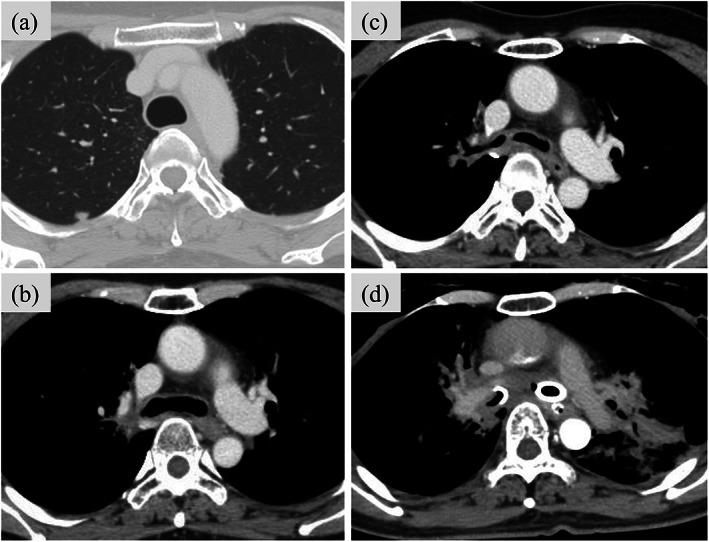

Adenoid cystic carcinoma (ACC) of the trachea is a rare disease that is slow growing and has a risk of distant metastasis. The standard treatment for ACC of the trachea is surgery, but this tumor is often unresectable. In definitive radiotherapy using photons for unresectable ACC of the trachea, it is sometimes difficult to deliver a sufficient dose to the target without exceeding the tolerable dose to the surrounding normal tissues. Here, we report two cases of ACC of the trachea that received a high dose (74 Gy [relative biological effectiveness]) of proton beam therapy and achieved long-term survival.

气管腺样囊性癌(ACC)是一种罕见的疾病,生长缓慢,有远处转移的风险。气管 ACC 的标准治疗方法是手术,但这种肿瘤往往无法切除。在使用光子进行无法切除的气管 ACC 的确定性放疗中,有时很难在不超过周围正常组织可耐受剂量的情况下将足够的剂量递送到靶区。在这里,我们报告了两例接受高剂量(74Gy[相对生物效应])质子束治疗的气管 ACC 病例,均实现了长期生存。